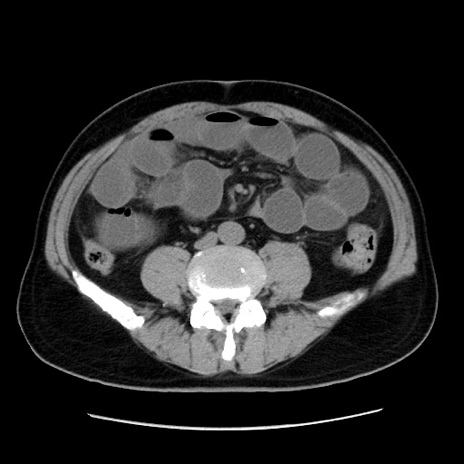

症例16(横断像)

【症例】 70歳代男性

【主訴】 腹痛、嘔吐

【現病歴】 約1ヶ月前より間欠的に腹痛と嘔吐あり、当院消化器内科を受診したところCTで多発する肝臓のLDAを指摘され、精査中であった。以降は消化器症状は安定していたが、2日前より嘔気と腹痛があり、同日より排便・排ガスが消失した。改善認めず、 本日、救急外来を受診した。

【既往歴】 大腸ポリープ切除後。

【身体所見】意識清明・会話良好、BT 36.3℃、BP 127/80mmHg、 P 80bpm、腹部:膨満あり、平坦・軟、上腹部正中および下腹部正中に圧痛あり、反跳痛なし、筋性防御なし。

【データ】WBC 7200、CRP 0.77